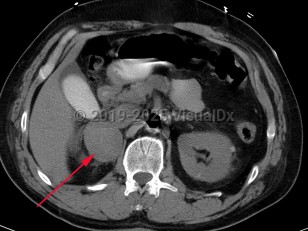

Imaging Studies image of Pheochromocytoma - imageId=7911948. Click to open in gallery.  caption: 'Patient presented with labile blood pressure. Unenhanced CT scan of the abdomen demonstrates a large complex right adrenal mass, surgically proven pheochromocytoma.'

Patient presented with labile blood pressure. Unenhanced CT scan of the abdomen demonstrates a large complex right adrenal mass, surgically proven pheochromocytoma.